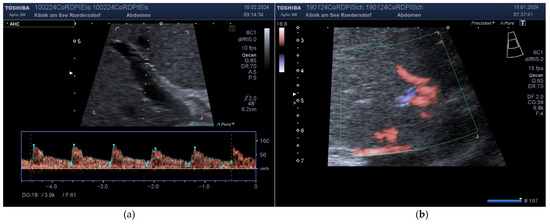

2.3.2. Location of the Probe, Insonation Angle, and Doppler Window